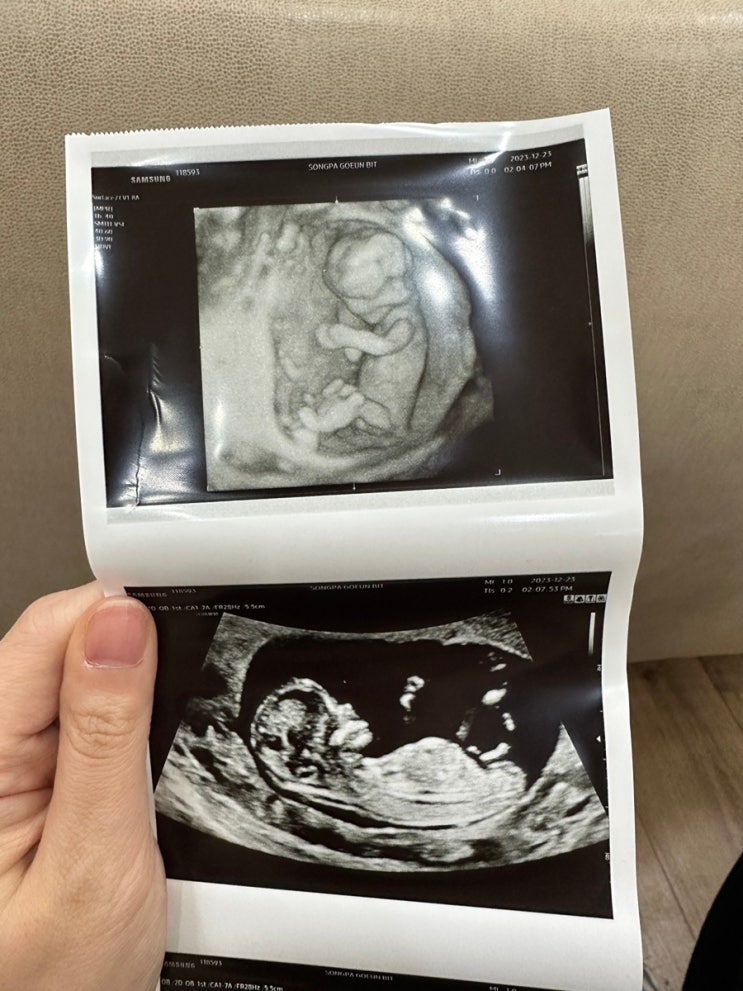

임신 13주차 기록 - 장꾸맘의 각도법, 각도법 성별 보는 법

안녕하세요 보리입니다. 새해가 코앞으로 다가왔네요 2024년은 다른해보다 특별한 해! 바로 보리를 만나는 ...